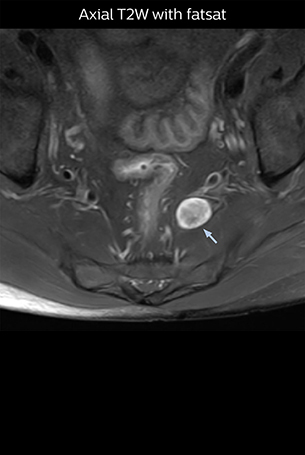

“Although symptoms of typical disc herniation and atypical hernia are very similar, the actual site of herniation is different. It is therefore important to characterize the nerve’s condition both inside and outside of the intervertebral foramina. “Conversely, if we see no abnormality in NerveVIEW, we can assume at least that there is no severe condition that requires surgery. Like this, it can help us avoid unnecessary surgery. NerveVIEW can have a tremendous impact in this way.”

“NerveVIEW is really useful for those cases where a nerve disorder is strongly suspected based on the clinical examination but our regular MRI images do not show any findings. These atypical herniations and spinal canal stenosis, occurring in 5% to 15% of the total lumbar herniation/stenosis cases are our main target when using NerveVIEW,” says Dr. Yabuki.

“The intra-luminal signal of veins, especially around the intervertebral space, can be suppressed well with NerveVIEW. As a result, we can easily observe the detailed nerve structure around the posterior ganglion,” he says. “This is why we use 3D NerveVIEW for intraforaminal stenosis and extraforaminal stenosis/herniation (lateral disc herniation). On the other hand, if herniation is suspected to exist inside the dorsal root ganglion (DRG), balanced TFE or ProSet-FFE is applied. NerveVIEW is not suitable for evaluating the median type of herniation.” The SE-EPI DWI-based method for MR neurography works well for large FOV exams like whole-body MRI, but focal examination of nerves is often limited by the attainable spatial resolution (both inplane and slice direction) and geometric distortion. “3D NerveVIEW achieves higher in-plane resolution – close to our other routine spine sequences – and the source images can be used instead of adding a fat-suppressed T2-weighted sequence,” Tanji says.

“NerveVIEW can clearly show nerve courses and presence of nerve compression. However, when multiple abnormalities are seen, it can still be hard to determine which nerve is causing the symptoms,” says Dr. Yabuki. “In our experience so far, we see abnormal findings on NerveVIEW in about 70% of elderly patients. As the pain is usually caused by only one nerve, we thus need to find the exact corresponding nerve.” “With a nerve root block, the patient's pain is improved by infiltration of local anesthesia directly around the nerve root considered to be responsible. Knowing such nerve root block findings prior to image interpretation, helps to easily recognize abnormal findings on NerveVIEW as well. In other words, without a priori knowledge, based on symptoms and/or nerve root block findings, we must be aware of the possibility of overdiagnosis.”